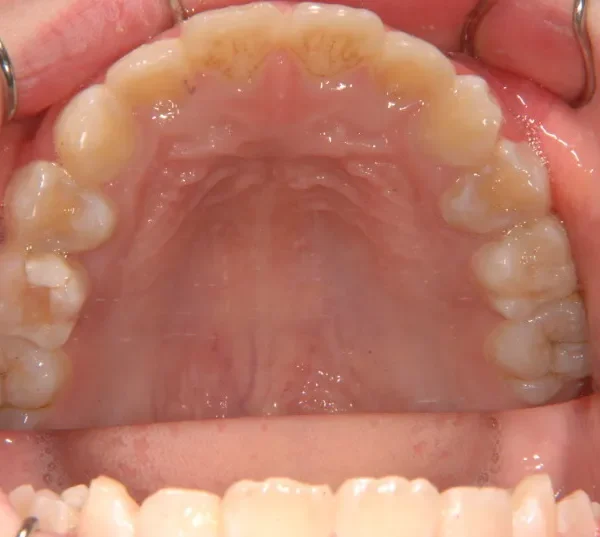

初診時年齢 小学校1年生 (女性) 主訴 受け口

診断名 叢生・反対咬合 装置名

状態 永久歯が生える隙間がない(叢生)

受け口(下顎前突/反対咬合)

下顎が大きい傾向があります。

上下の真ん中にズレがあるのと、上下とも永久歯の生えるスペースがせまいため、オリジナル矯正装置でスペースを作り、受け口も改善していきます。